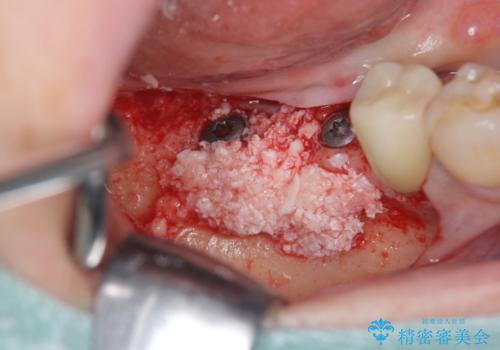

インプラント治療を行うにあたり周囲に骨を造成することで安定して噛める環境の整備を計画します。

今回はインプラント埋入時に固定が得られたので同時に骨の造成を行い治療を進めることができました。